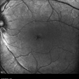

- retinal dystrophy

- Scanning laser ophthalmoscope

- 34 year old male with colour blindness and loss of visual field